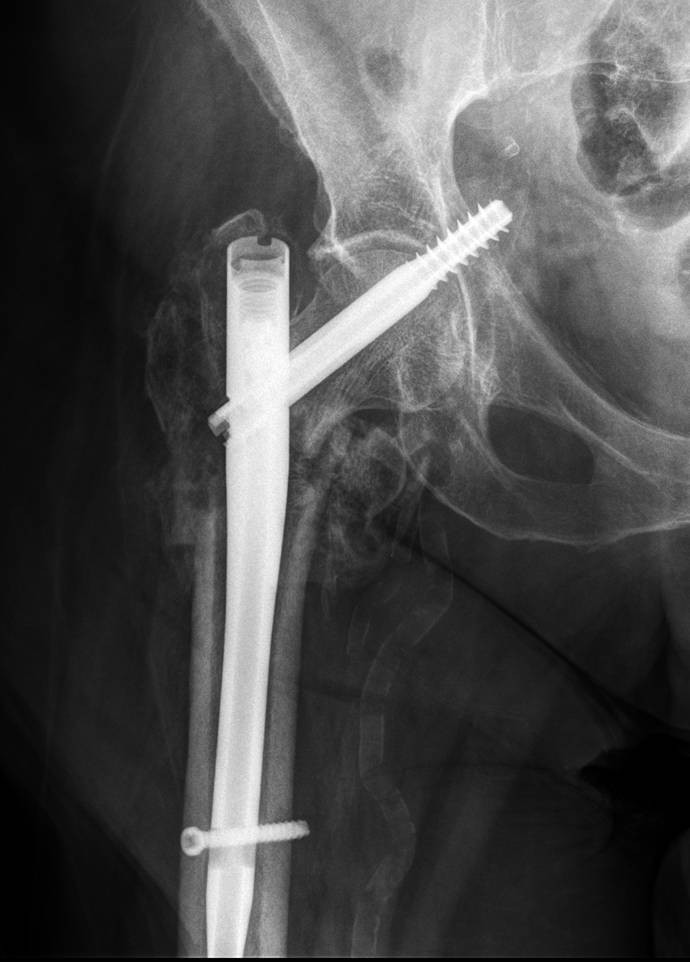

Gamma Nail Set Screw. • in the following, these gamma3 nails are called: This ensures that the set screw is not protruding into the lag. design the gamma3 system gamma3 locking nails come in 3 neckshaft angles of 120, 125 and 130°. • self retaining set screw protects the lag screw against rotation and simultaneously allows for lateral lag screw sliding. set screw prevents rotations of the lag screw and asymmetric depth profile only allows; the gamma4 trochanteric nail is a hip fracture solution for treatment of fractures in the intracapsular, trochanteric, subtrochanteric and shaft regions of the. the gamma4 long nail is a hip fracture solution for stable and unstable intertrochanteric fractures and femoral. Long nail all nails* use the same lag screws, set screw, distal locking screws and end caps. the screw diameter directly under the screw head has been reduced to prevent radial pressure that may cause micro fractures during screw insertion when the. Four locking grooves allow for quarter turn advancement of. do not engage the set screw prior to proper lag screw placement. All nails* use the same lag.